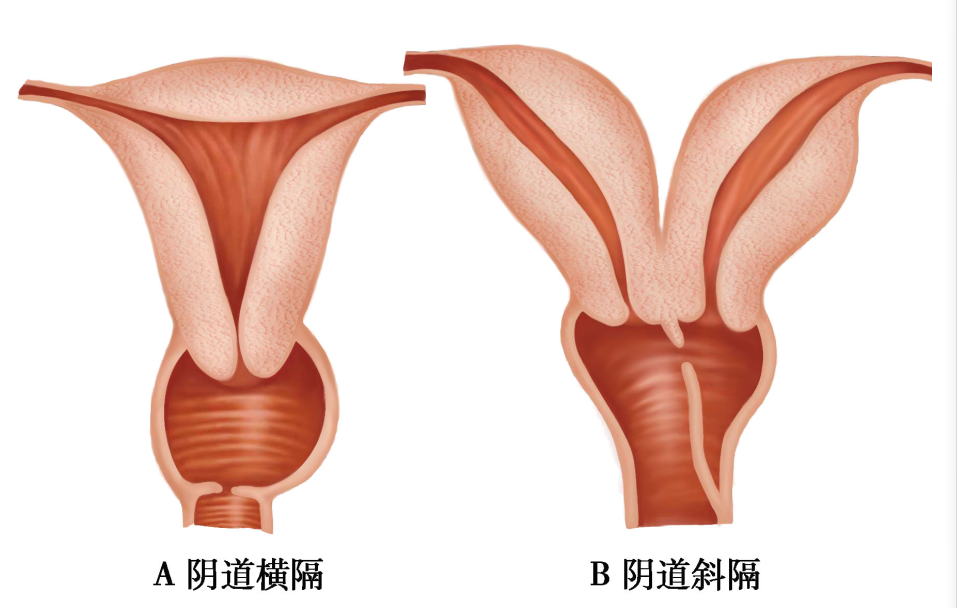

(三)阴道横隔( transverse vaginal septum)

为两侧副中肾管会合后的尾端与尿生殖窦相接处未贯通或部分贯通所致。很少伴有泌尿系统和其他器官的异常,横隔位于阴道上、中段交界处为多见。阴道横隔无孔称完全性横隔,隔上有小孔称不全性横隔(图22-1)。不全性横隔位于阴道上段者多无症状,位置偏低者可影响性生活,阴道分娩时影响胎先露部下降。完全性横隔有原发性闭经伴周期性腹痛,并呈进行性加剧。妇科检查见阴道较短或仅见育端,横隔中部可见小孔,肛诊时可扪及宫颈及宫体。完全性横隔由于经血潴留,可在相当于横隔上方部位触及块物。

图22-4 阴道横隔示意图

图22-5 阴道异常

治疗为手术切除横隔,缝合止血。分娩时,若横隔薄者可于胎先露部下降压迫横隔时切开横隔,胎儿娩出后再切除横隔;横隔厚者应行剖宫产术。术后要定期扩张阴道或放置阴道模具,防止横隔残端窄缩。